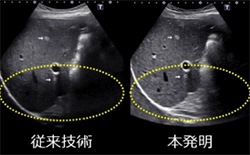

発明技術:周波数が異なる複数の基本波を同時に送信し,基本波が体内を伝播する際に組織から発生する差周波を,第2高調波と効果的に干渉させる(図1)。これにより,映像化する超音波の周波数帯域が低周波数側に広がったため,深部組織の映像化が可能になり,映像の解像度が向上した(図2)。また,差周波と第2高調波の周波数分布が打ち消し合わないよう,送信する基本波の周波数と位相を制御して感度を高めた。

図1 本発明の原理

図2 従来技術と本発明の超音波画像